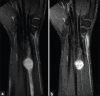

Schwannomas are benign soft-tissue tumors that arise from peripheral nerve sheaths throughout the body and are commonly encountered in patients with neurofibromatosis Type 2. The vast majority of schwannomas are benign, with rare cases of malignant transformation reported. In this pictorial review, we discuss the magnetic resonance imaging (MRI) appearance of schwannomas by demonstrating a collection of tumors from different parts of the body that exhibit similar MRI characteristics. We review strategies to distinguish schwannomas from malignant soft-tissue tumors while exploring the anatomic and histologic origins of these tumors to discuss how this correlates with their imaging findings. Familiarity with the MRI appearance of schwannomas can help aid in the differential diagnosis of soft-tissue masses, especially in unexpected locations.